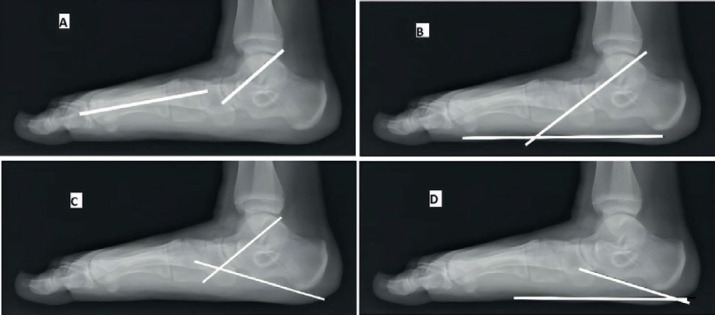

Methods: This is a prospective study and included 26 feet in 19 patients who underwent subtalar arthroereisis for symptomatic flexible flatfeet deformity. Preoperative and postoperative functional assessment based on the American Orthopedic Foot and Ankle Society (AOFAS) hindfoot scale. Radiographic parameters included preoperative and postoperative Kite`s angle, talonavicular coverage angle, Anterior-Posterior talo-1st metatarsal angle, Meary`s angle, talar declination angle, calcaneal inclination angle and lateral talocalcaneal angle.

Results: The mean follow-up period was 22.5±9.4 months and the mean preoperative AOFAS score was 54.6±6.0, while the mean AOFAS score at the last follow-up visit was 86.3±3.9 (P<0.001).The mean preoperative and postoperative radiological measurements were 19.0°±8.2° and 7.4°±3.9° for the AP Talo-1st metatarsal angle (P<0.001); 23.6°±9.1° and 8.0°±4.0° for talonavicular coverage angle (P<0.001); 35.4°±3.7° and 24.1°±3.4° for Kite`s angle (P<0.003); 22.4°±6.1° and 7.5°±3.7° for Meary`s angle (P<0.001); 41.0°±4.4° and 25.2°±7.1° for talar declination angle (P<0.001); 13.5°±3.7° and 21.3°±3.6° for calcaneal inclination angle (P<0.001) and 52.4°±7.2° and 42.9°±4.8° for lateral talocalcaneal angle (P<0.041) respectively.